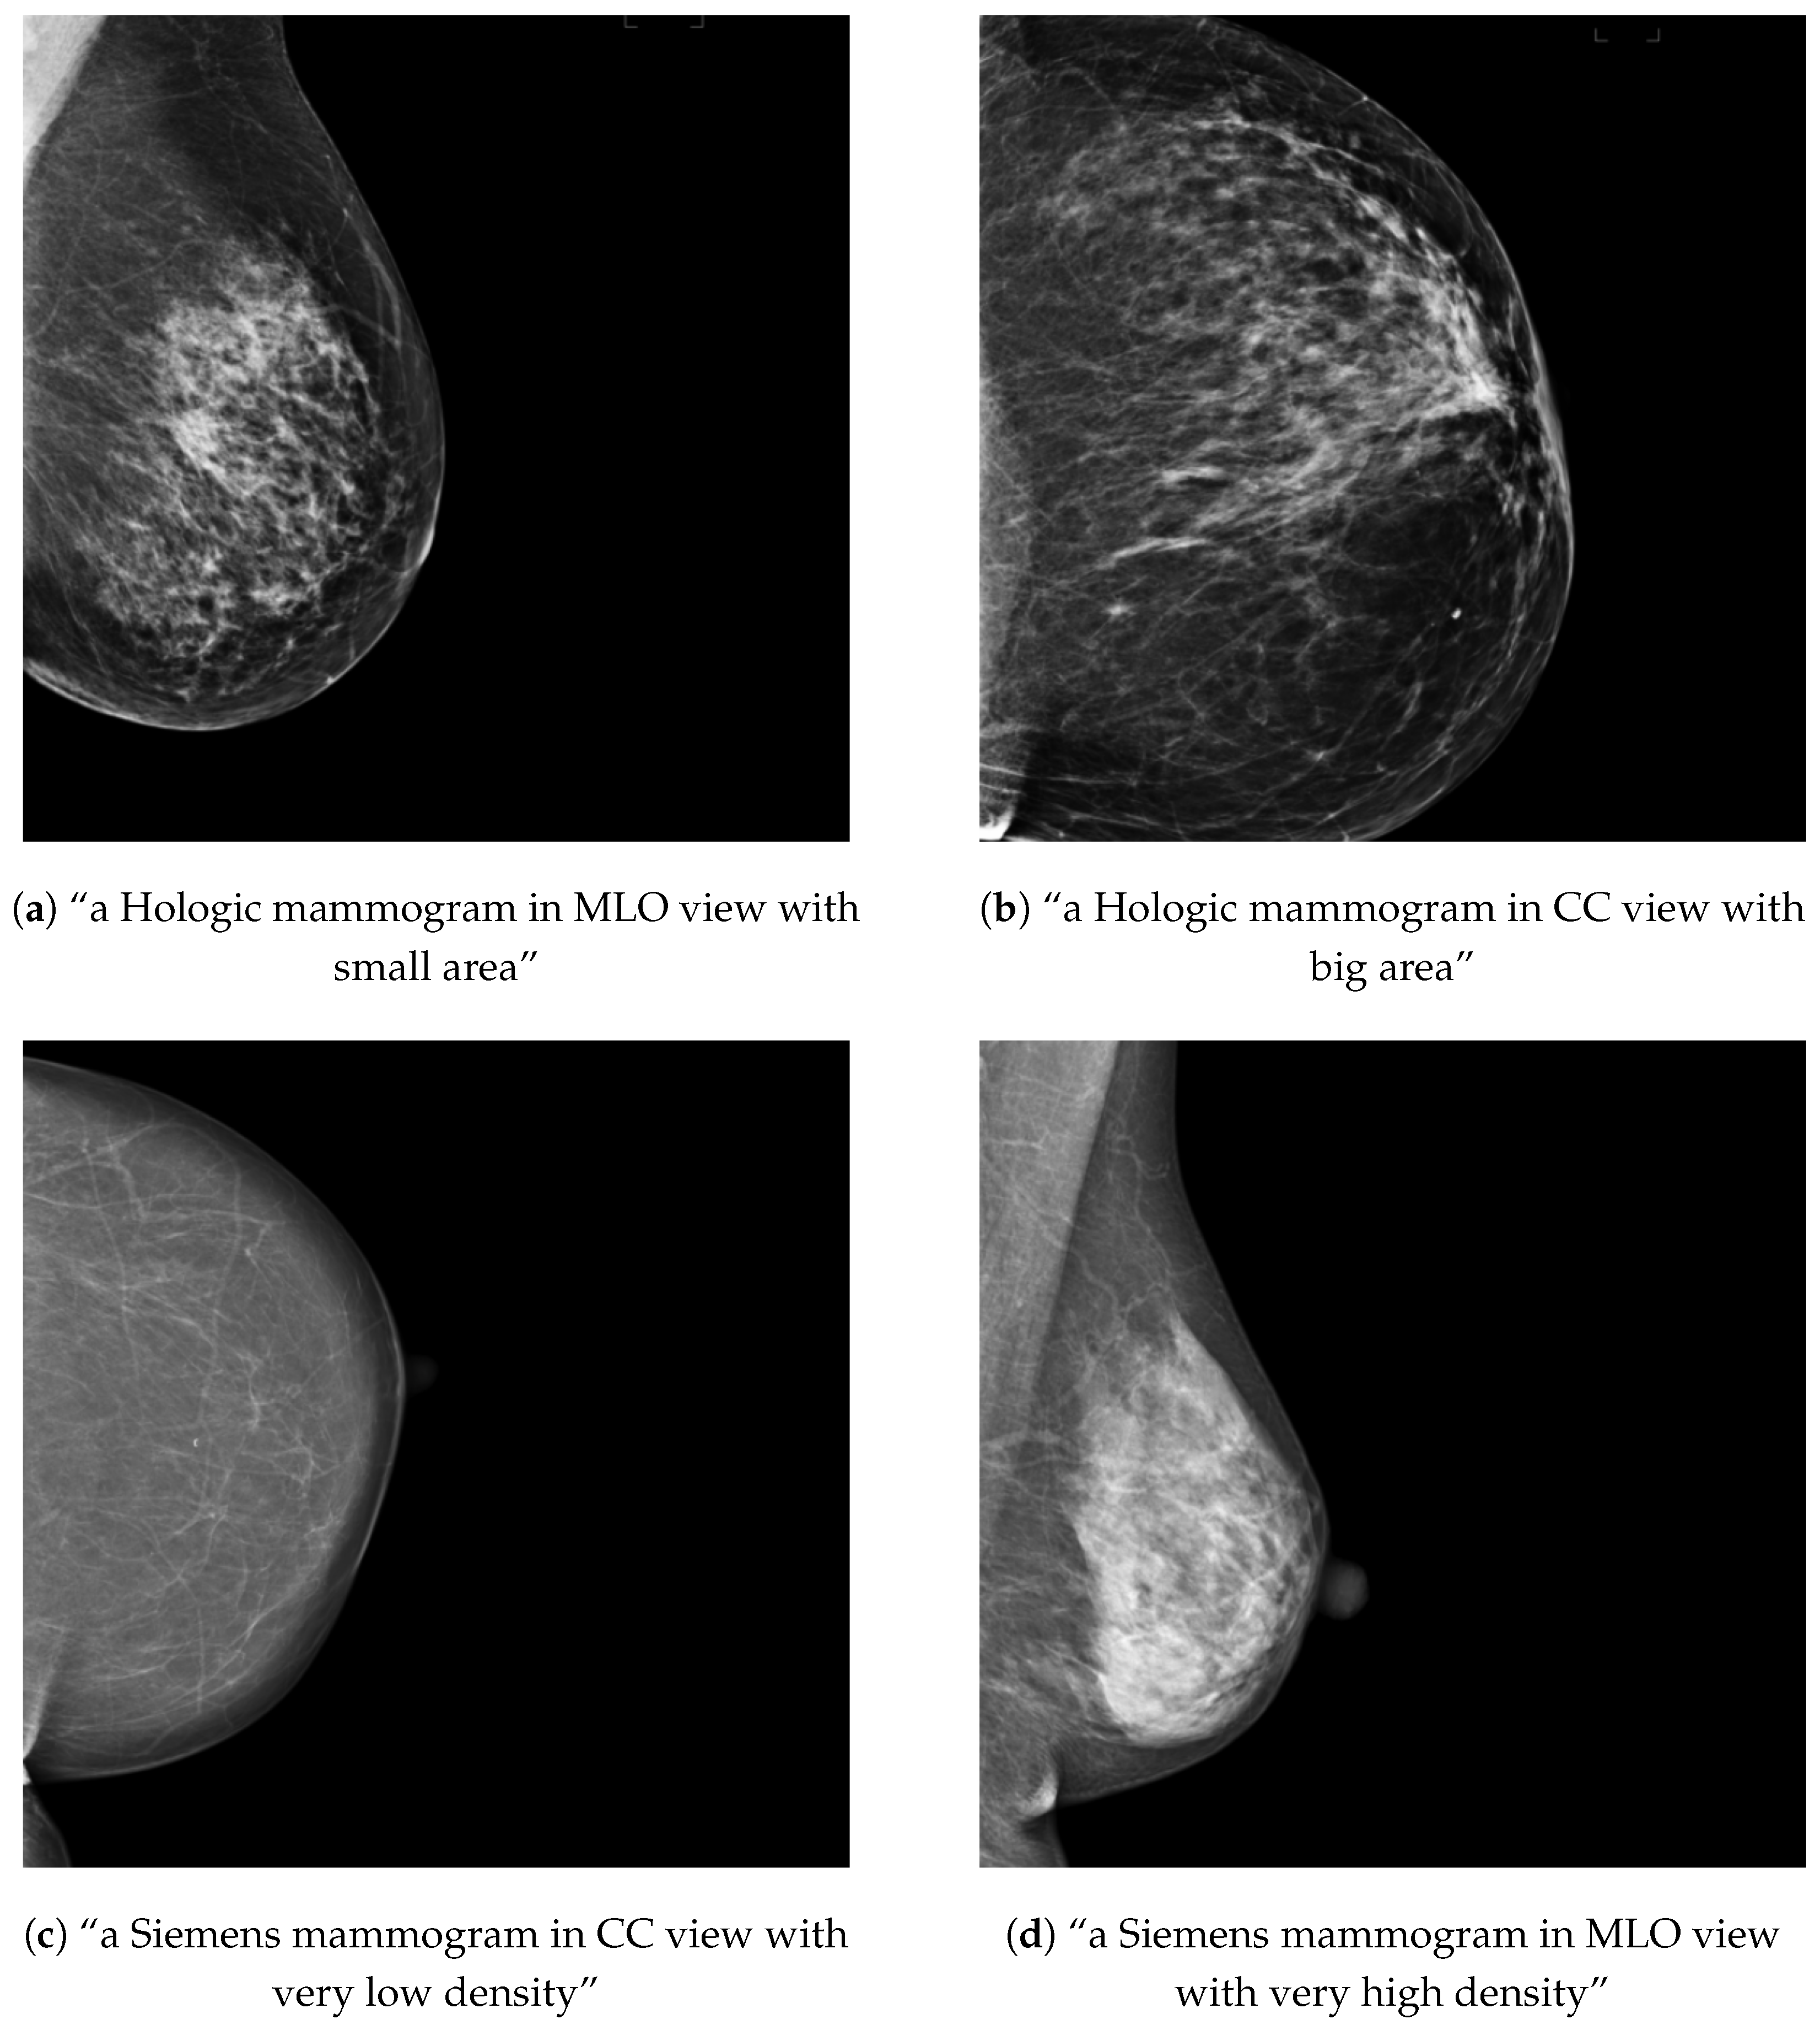

3.1.1. Conditional Models

3.1.2. Joint OMI-H and VinDr Model: Concept Extrapolation